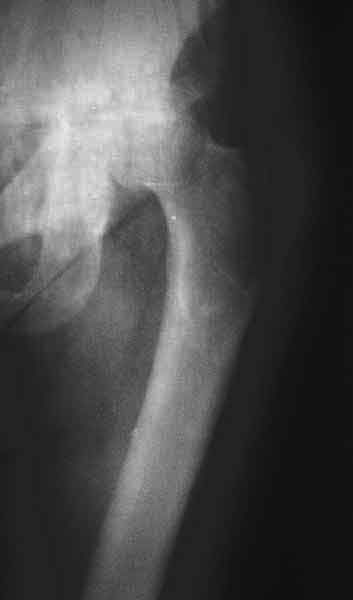

AV> опираясь на стул. На ногу не наступает. Укорочение 8 см. Иногда

А за счет чего такое укорочение? По снимку не видно соответствующего дефекта. Ну плюс приводящая контрактура - но все равно как-то уж больно много. Может, сделать снимки и таза обзорный с обоими проксимальными отделами бедра, и коенный суставов с приложенной линейкой какой?

Судя по снимку, максимум истинное укорочение около 4 см, что может быть коррегировано интраоперационно. Вопрос в другом: куда ставить ацетабулярный компонент в истинную или во вновь сформированную ( впадина диспластичная).

Невозможно не согласиться с Анатолием, чтобы заниматься адекватным планированием как минимум прямая проекция таза должна быть сделана, как

максимум для оценки состояния мышц( насколько реально возможно низвести бедро) прямая проекция таза с тракцией за больную ногу.

По рентгенограммам укорочение не более 4 см, остальное возможно за счет контрактуры. Опыта с низведением аппаратом Илизарова нет, но мы одномоментно такие укорочения корригировали вполне успешно (в год 5-10 именно таких и проходит). Лишние этапы пожалуй только будут способствовать инфекции. Доступ чаше применяем передне-наружный, а вот протез наверное поставили бы здесь на цементе - остеопороз выражен.

The X ray that you provided does not show 8 cm of shortening. Perhaps you could send one showing the whole pelvis and proximal femurs.

I agree with Dr Eid's comments. The origin of the 8 cm leg length difference is a puzzle. Is this a clinical measurement? In that case contracture of the joint might affect the measurement. Can we see an AP pelvis to include both hip joints (including a calibration object with a known length) so that the difference in leg lengths that can be ascribed to the hip deformity and bony reabsorption can be measured. This sort of xray will help with templating for the TJR also. I would be very tempted to do a one stage procedure and accept some shortening. Shoe lifts should take care of a 3-4 cm difference.

До травмы проблем с ногой не было. Укорочения, болей и т.п. не отмечал. Сегодня перемерял укорочение - меньше 7 см намерять не

получается :)

По уровню малых вертелов (с учетом рентгеновского увеличения) получается 5 см. Клинически ногу низвести путем тракции невозможно. Из движений - сгибание до 40*, остальные движения "символические".

Ортопедическое укорочение пострадавшей ноги может быть и 7, и 10 см. за счет контрактур в тазобедренном суставе, а вот истинное укорочение, судя по представленным рентгенограммам, вряд ли больше 4 см.